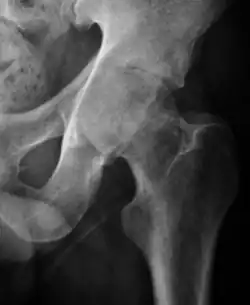

Projectional radiography ("X-ray") is the first imaging technique of choice in hip pain, not only in older people with suspected osteoarthritis but also in young people without any such suspicion. In this case plain radiography allows categorization as normal hip or dysplastic hip, or with impingement signs, pincer, cam, or a combination of both.[1]

X-Ray

Projectional radiography ("X-ray") is currently useful not only in older people in whom osteoarthritis of the hip is suspected but also in younger people without osteoarthritis, who are being evaluated for femoroacetabular impingement (FAI) or hip dysplasia.[1]

Plain radiography allows us to categorize the hip as normal or dysplastic or with impingement signs (pincer, cam, or a combination of both). Besides these, pathologic processes like osteoarthritis, inflammatory diseases, infection, or tumors can also be identified (Figure 1).[1]

Figure 1.

-

Radiography in normal hip -

X-ray in pincer impingement type of hip dysplasia -

X-ray of cam -

Hip in osteoarthritis -

Septic arthritis

![Figure 2A. Normal hip.[1]](./_assets_/X-ray_of_measurements_on_a_normal_hip.jpg)